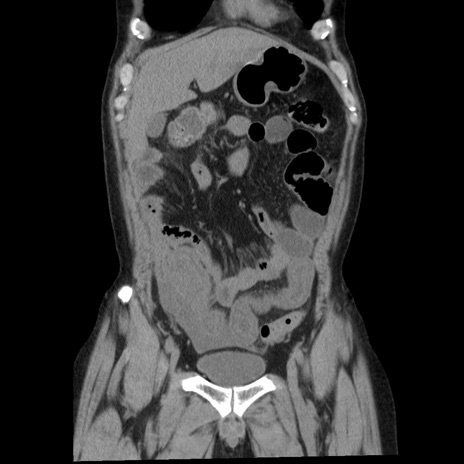

症例29(冠状断像)

【症例】40歳代男性

【現病歴】2日前から胃痛あり。徐々に周期的な激痛に変化した。本日になっても激痛があるため受診。

【身体所見】意識清明、BT 38-39℃台あり、腹部:膨満、やや硬、右下腹部に圧痛あり。

【データ】WBC 8500、CRP 23.26